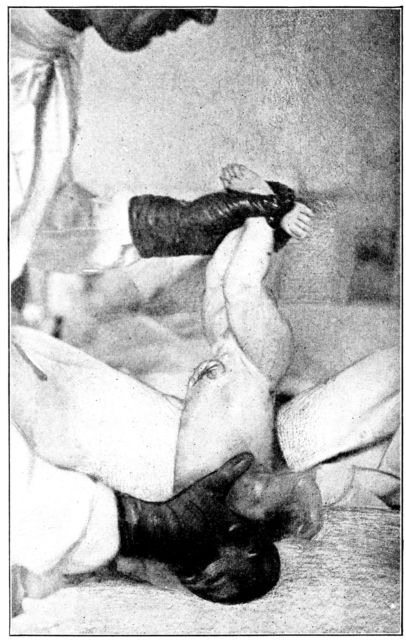

| 155. | Preparation for circumcision | 468 |

| 156. | Baby draped with sterile sheet, in above | 469 |